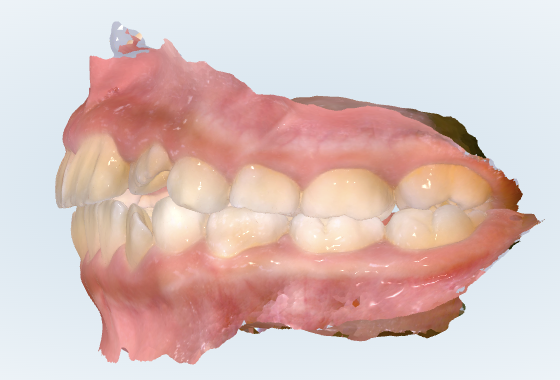

初診時の画像診断

上下の歯並びにガタガタがあります。

咬み合わせに出っ歯の傾向があります。